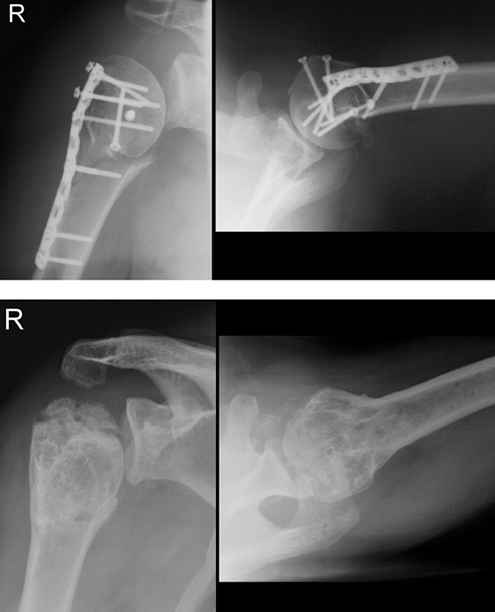

Рис. 31-11. из Rockwood & Green "Fractures  in adults" (2006).